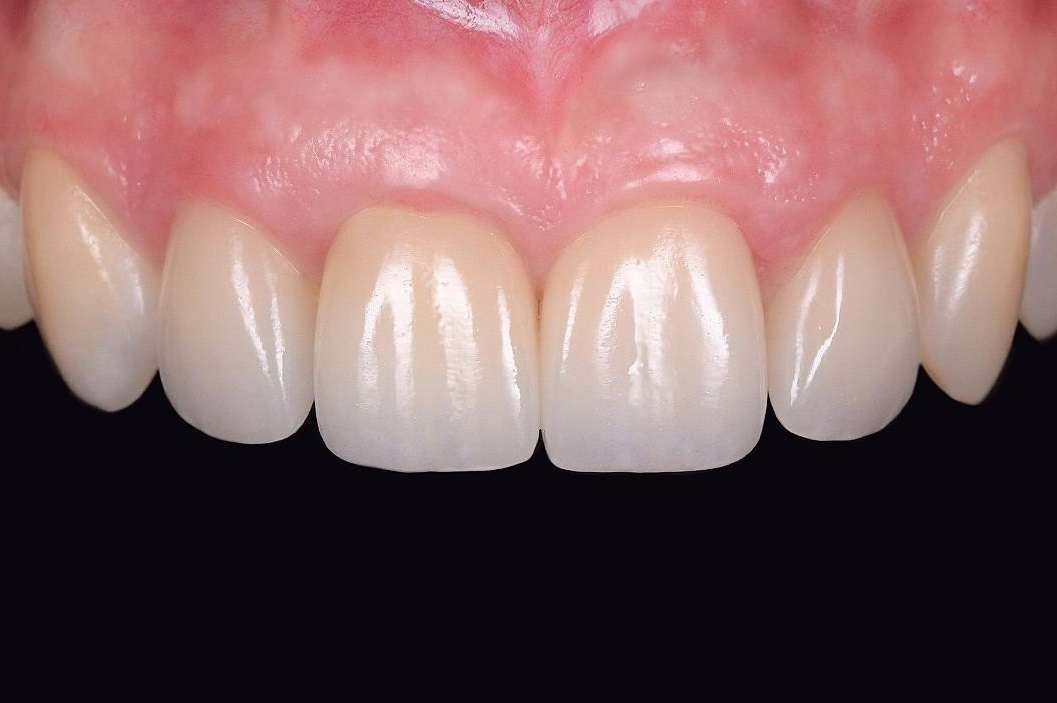

• Ưu điểm thứ 2: Thẩm mỹ.

Thẩm mỹ của kỹ thuật cấy ghép imlant cá nhân hóa DCT được nhìn qua 2 lăng kính.

Ưu điểm thẩm mỹ thứ nhất: Thẩm mỹ lợi và mô nha chu đẹp nhất.

Việc sử dụng Healing Customized để tạo hình và tái lập mô nha chu, sử dụng Customzied Abutment để định hình giúp răng implant có nhân hóa có mô nha chu uốn lượn như răng thật, mang lại thẩm mỹ hồng tốt hơn so với răng implant truyền thống.

Ưu điểm thẩm mỹ thứ 2: Thẩm mỹ màu sắc và hình thể răng tự nhiên và bền màu.

Thay vì sử dụng sứ đắp và sten màu như các loại răng toàn sứ trước đây, 3D Pro ML sử dụng các thông số màu cài đặt sẵn, sắp xếp từ lớp phân tử, giúp cho mức độ ổn định màu rất cao, hiệu ứng màu rất giống răng thật.